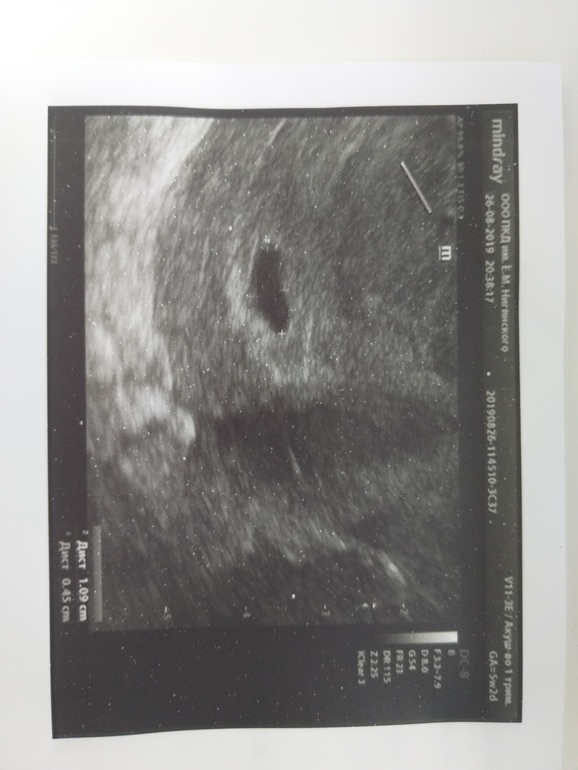

Вчера была у доктора, по результатам анализов направила меня на узи (срок 5 нед. 1 день или 22 ДПО)

Врач увидел только плодное яйцо, эмбрион и желточный мешок не визуализируются.